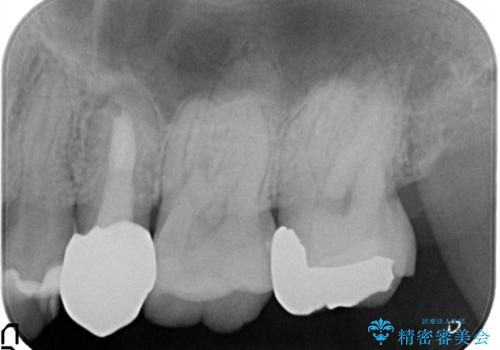

- 左上の後ろから3番目の歯のかぶせ物が適合不良であったので、根管治療を行い、オールセラミックを装着する計画としました。

またその隣の目立つ銀歯も同時に、セラミックに交換することとしました。

根管治療からかぶせ物まで精度の高い治療をおこないました。